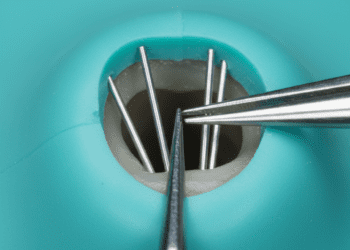

Nos casos mais avançados, a odontologia restauradora oferece opções como resinas compostas, facetas, coroas e outras restaurações que protegem o dente, recuperando forma e função. A escolha do material e técnica depende da extensão da erosão, da localização dos dentes afetados, da estética e da função mastigatória.